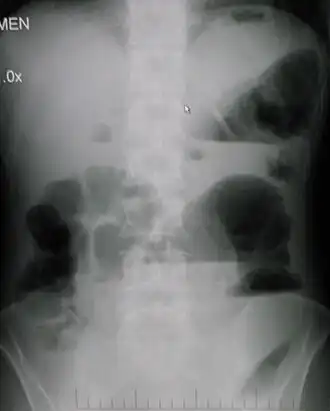

• Рентгенография брюшной полости

• определение газа и уровней жидкости в петлях кишок (чаши Клойбера)

• поперечная исчерченность кишки (симптом керкринговых складок)